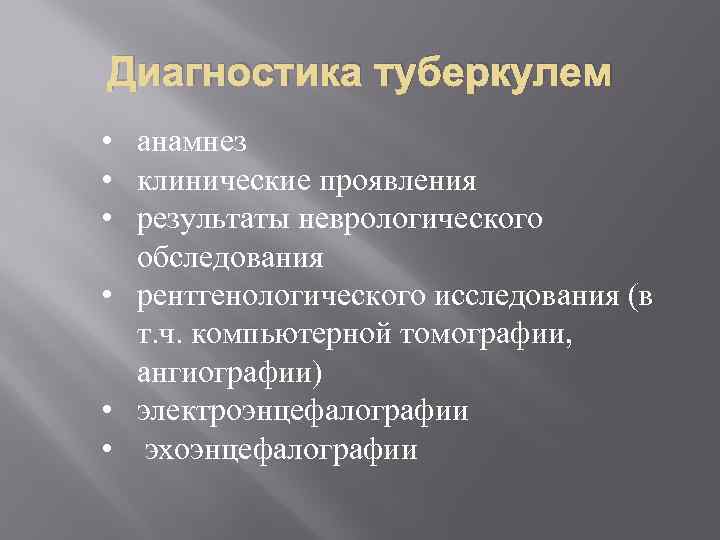

Диагностика туберкулем • анамнез • клинические проявления • результаты неврологического обследования • рентгенологического исследования (в т. ч. компьютерной томографии, ангиографии) • электроэнцефалографии • эхоэнцефалографии

Диагностика туберкулем • анамнез • клинические проявления • результаты неврологического обследования • рентгенологического исследования (в т. ч. компьютерной томографии, ангиографии) • электроэнцефалографии • эхоэнцефалографии